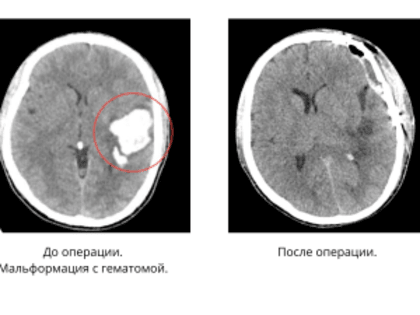

Врачи спасли 18-летнего россиянина с гематомой в мозге

Операция прошла успешно. Врачи Московского областного научно-исследовательского клинического института имени М.Ф.